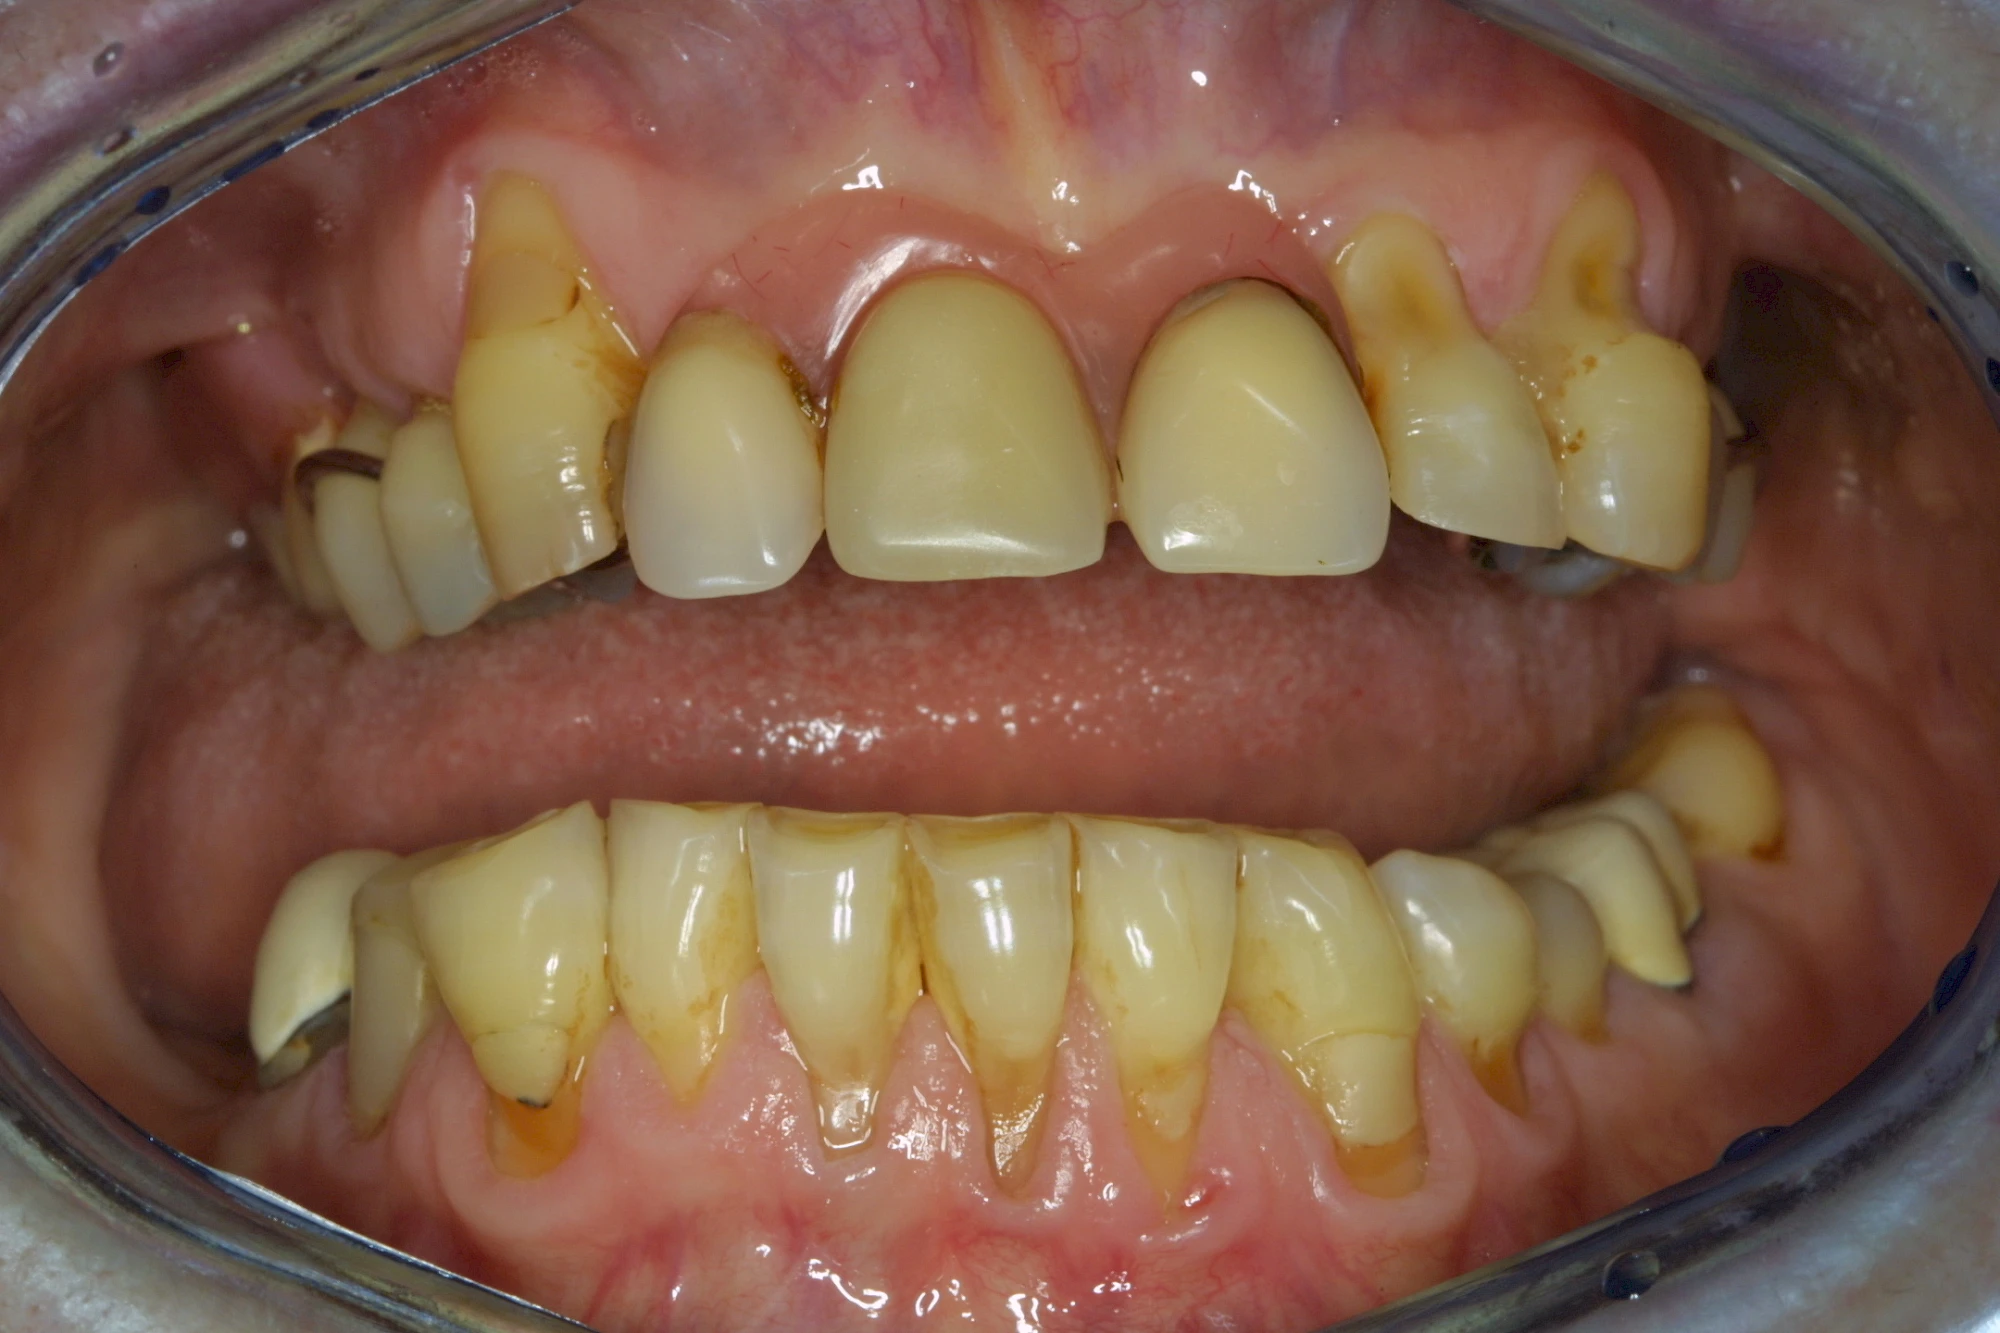

Auswaschung

Auswaschung (Erosion) dagegen ist eine Verschleißerscheinung der Zähne aufgrund von immer wiederkehrenden Säureangriffen durch die Nahrung, verstärkt zum Beispiel durch den Genuss säurehaltiger Getränke oder Speisen. Auch bei Menschen mit einer Essstörung (z. B. Bulimie) können die Zähne durch die Magensäure ausgewaschen erscheinen.

Keilförmiger Defekt

Eine Sonderform sind sogenannte keilförmige Defekte im Bereich der Zahnhälse. Hier geht man davon aus, dass Knirschen und Pressen in Kombination mit falschen Putzgewohnheiten (zu hoher Putzdruck, Verwendung von Zahnpasta mit hohen Abrasionswerten) eine Rolle spielen.